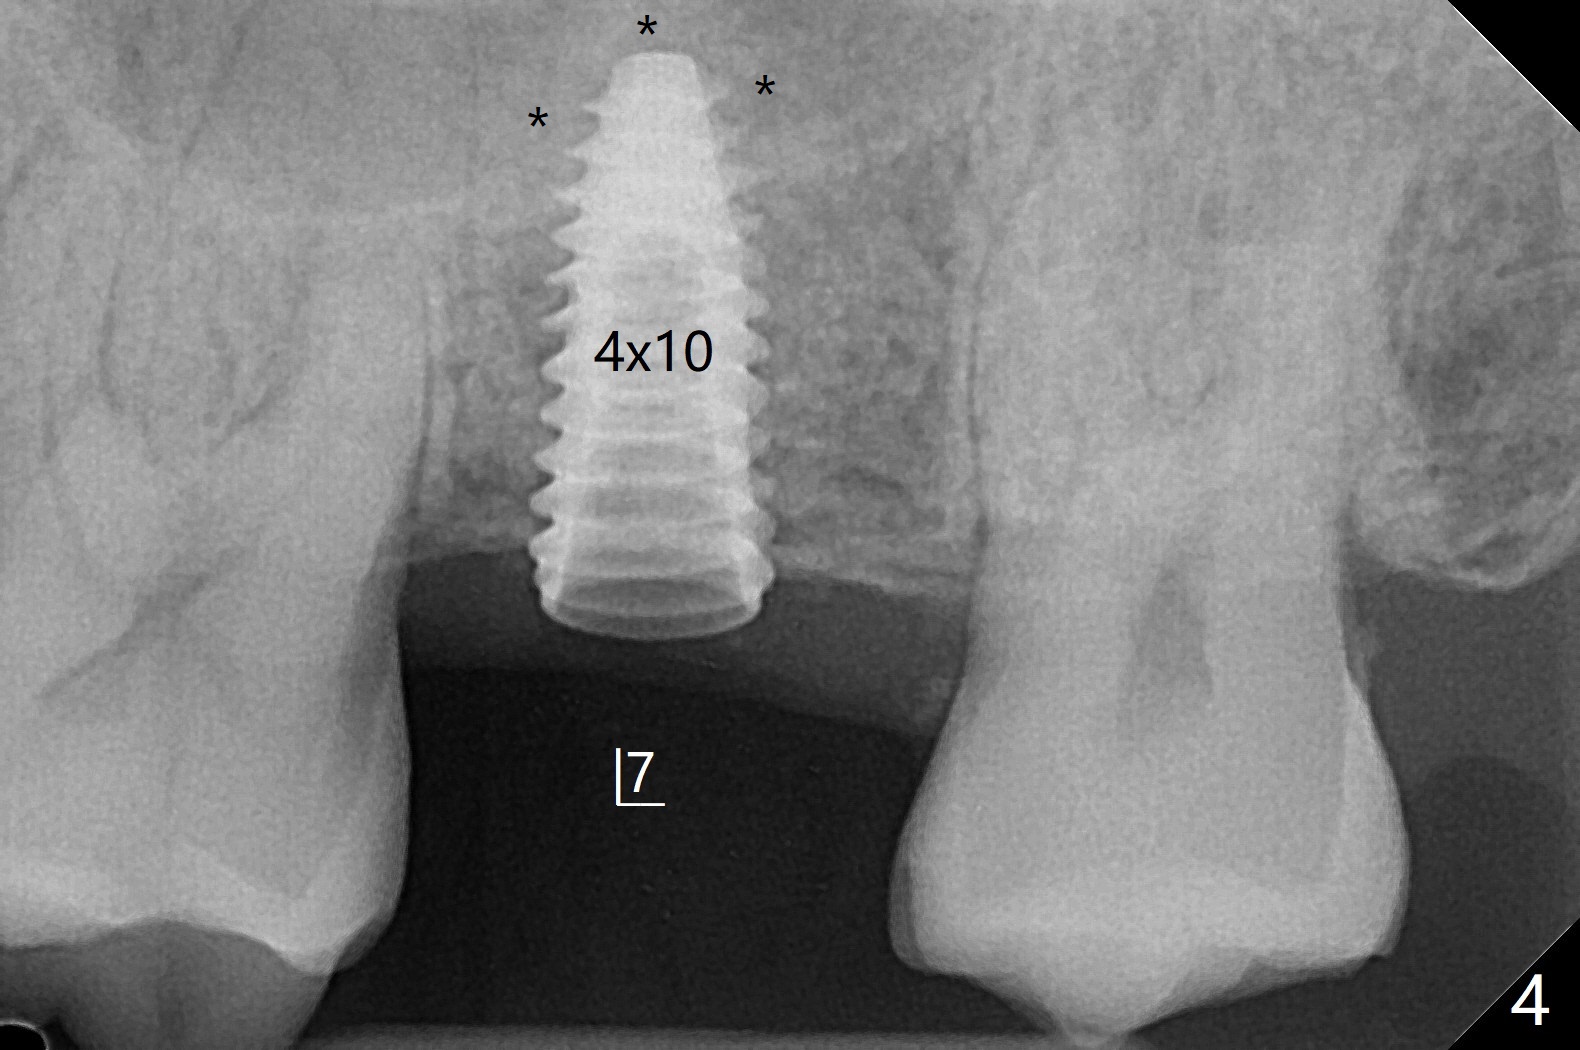

66岁男右上,左上7导板延期种植(足够角化龈,使用环形切刀),都提升,但是前者未植骨(图一,二(骨高度多,进入上颌窦少)),后者植骨(图六(*),七),由于扭力低(小于15Ncm),放置愈合螺帽和剪成圆形六个月胶原膜,使用牙周胶水(图三,八),之后不再放置牙周敷料。当钻头接近左侧上颌窦底板时,放置骨粉(图四-六:*),使用报废植体(图四,五)和正式植体(图六)将骨粉推入上颌窦。术后病人抱怨食物撞击伤口疼痛,即刻修复减少术后疼痛。术后5个月没有骨质吸收,基台完全就位(图十一,二)。